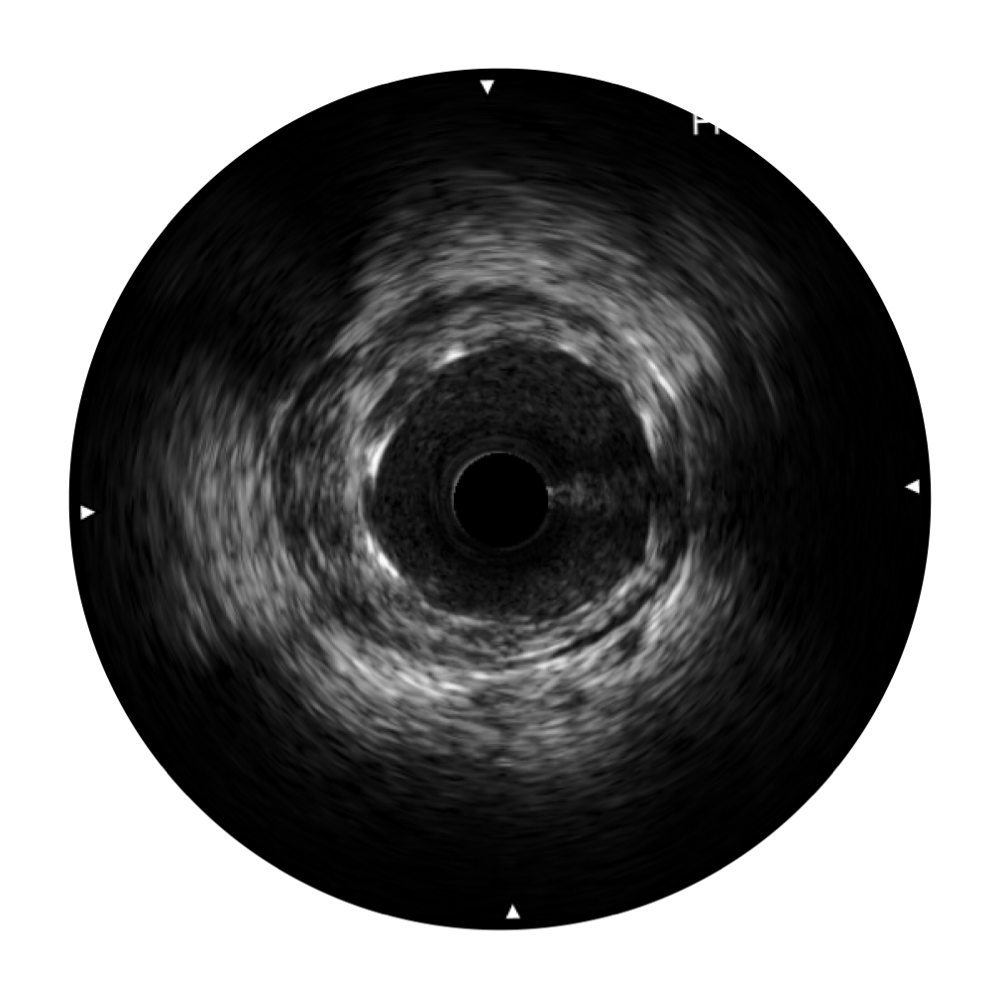

• db真人体育官网宽频IVUS图像

• 传统IVUS图像

对比传统IVUS导管成像,db真人体育官网宽频IVUS图像的近场支架梁显影更细腻,远场中膜外血管仍清晰可辨,兼顾远中近,兼顾分辨力与穿透深度